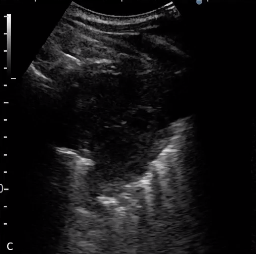

由于气体的干扰,超声引导下的肺活检仅对肺周边病灶进行

甚至有报告,某些经皮穿刺活检周围肺病变的超声(US)引导优于CT引导。但是,即使是有经验的超声医生也不一定适合所有的临床场景,也不一定适用于由具有不同经验的医生执行的患者的所有临床实践。

![]() 对于周围肺病变,无论其直径大小或胸膜接触长度如何,超声导向的肺穿刺活检可能是一种安全有效的诊断工具。 病例介绍